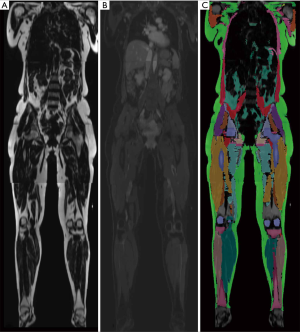

Parallel to advantages in the application of CT for BCP tasks, MRI has gained comparable importance in the assessment of body compartments, muscle mass, and associated anthropometric measures. The technique is free of ionizing radiation and therefore allows repetitive scans in specific longitudinal observations. Furthermore, free from several technical biases or errors in DEXA and CT, MRI has been validated to reliably measure body compartments (16,17), and to perform this task at high accuracy, given a range of quantitative error of 1.1% to 4.4% (18). This error may also depend on basic acquisition parameters, such as the use of surface or body coils or other protocol decisions (e.g., continuous moving table acquisition; see Table 1 for exemplary protocol) with implications on signal-to-noise ratio and acquisition time. This must be considered and handled individually, as an error of a few percent may be negligible for certain populations and indications while playing a significant role in e.g., monitoring examinations of athletes. In any case, despite its validity and reliability, MRI currently faces difficulties in availability and ease of use in terms of data assessment. The big advantage of muscle assessment by MRI, namely acquisition of whole-body data, demands technically difficult and still time-consuming post-processing. Manual segmentation, as shown in Figure 1 takes several hours (depending on the volume, accuracy, and detail of segmentation) but is currently not ready-for-use in clinical practice. Numerous automated methods intend to ease whole-body segmentation (20-22), but except for very limited proprietary examples, the majority of BCP assessment by whole-body MRI is currently performed in research settings employing artificial intelligence for advanced segmentation tasks with promising results (Figure 2).

The principle of chemical shift imaging is based on different precession frequencies of water and fat protons at a certain magnetic field strength. This allows acquiring in- and opposed-phase images where proton spin magnetization vectors at two different echo times (i.e., two-point technique) are either in equal or opposed direction to each other. Respective signal intensities can then be used to additionally generate fat and water images (Figure 1), resulting in four different image contrasts in total. This principle was first described by Dixon in 1984 (34) and is nowadays widely used in clinical imaging. The Dixon technique due to its robustness, in general, does offer homogeneous fat-saturation over a large field of views, as well as fast MR imaging of large target volumes, e.g., whole-body (wb) MR imaging when used with gradient-echo sequences (35-37). However, limitations have to be considered, as especially fast two-point Dixon sequences are prone to B0-magnetic field inhomogeneity (38). There are however different strategies in reducing this error. On one hand, multi-echo Dixon techniques compensate for these inhomogeneities, allowing to accurately quantify fat content in any image voxel through fat-fraction maps where the grey value of each pixel is proportional to its respective fat-percentage (39). This technique is most widely used for quantification of liver steatosis and has shown to be comparable to a histologic reference standard (40,41). The same technique has also been applied to muscle imaging and in a recent study fatty infiltration of rotator cuff muscles was quantified with isotropic fat-fraction maps from multi-echo 3D-Dixon sequences and correlated with post-operative outcome measures (42), indicating the direction of advanced muscle quality assessment with quantitative MR imaging. On the other hand, certain methods for B0-magnetic field inhomogeneity reduction focus on the use of prospective and retrospective intensity inhomogeneity correction. Exemplarily, Andersson et al. proposed a self-calibrating correction method that allows for the processing of raw as well as normalized images with regard to B0 magnetic field inhomogeneities (43).